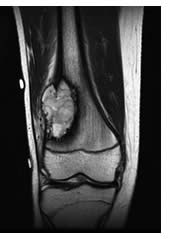

Tumore della lingua diagnosi terapia tumore dott.G. Sintomi del tumore della lingua. Il tumore alla lingua può presentarsi (come per il tumore della bocca) come una macchia rossa (eritroplachia) o come una macchia bianca (leucoplachia); altre volte si può presentare sotto forma di una lesione che non guarisce e che può provocare la fuoriuscita di sangue dalla cavità orale.. Spesso durante la masticazione o la deglutizione compare un dolore.

Tumore alla lingua come si manifesta, i sintomi e la terapia. In altri casi si riscontra la presenza di una lesione che tende a non guarire, provocando anche perdita di sangue dalla bocca. Inoltre spesso in chi è colpito da un tumore alla lingua la. Tumore dello stomaco cura, sintomi e malattia. Il tumore dello stomaco si presenta con sintomi che possono facilmente essere confusi con quelli di una gastrite o di un'ulcera gastrica nausea, difficoltà di digestione, mancanza di appetito o difficoltà a mangiare grandi quantità di cibo. Come si produce un vaccino ed altro mednat. Produzione dei vaccini facoltativi e non con cellule cancerose infettate vedi cosa e' un vaccino ? Il vaccino è un preparato di laboratorio, contenente materiale costituito da proteine di lipidi, complesse, a dna, eterologhe, cioè estranee, provenienti da microrganismi o parti di essi (organi e/o tessuti). Tumore alla prostata, sintomi, metastasi, cure e mortalità. Il tumore alla prostata maligno è uno dei tipi di cancro più frequenti diagnosticati negli stati uniti e si presenta soprattutto negli uomini che hanno oltrepassato i 65 anni d’età.. La prostata è una ghiandola propria solo dei maschi che si trova appena sotto la vescica (un organo che raccoglie l’urina); avvolge l’uretra (il tubo che trasporta l’urina dalla vescica affinché sia. Tumore della lingua diagnosi terapia tumore dott.G. Sintomi del tumore della lingua. Il tumore alla lingua può presentarsi (come per il tumore della bocca) come una macchia rossa (eritroplachia) o come una macchia bianca (leucoplachia); altre volte si può presentare sotto forma di una lesione che non guarisce e che può provocare la fuoriuscita di sangue dalla cavità orale.. Spesso durante la masticazione o la deglutizione compare un dolore. Tumore della bocca diagnosi e terapia tumore dott.G.Spinelli. Successivamente è fondamentale inquadrare il performance status (le condizioni generali del paziente, ovvero come si presenta il paziente prima dell’ intervento chirurgico) del paziente attraverso esami ematici. L’operabilità del tumore della bocca dipende dall’estensione locale e dalla presenza di metastasi locoregionali o a distanza.